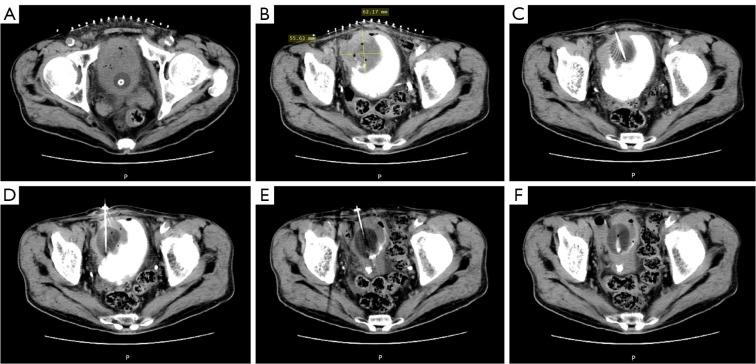

A literature search was performed in the PubMed database for articles published in English between 2001 and 2024. The keywords used were: "muscle-invasive bladder cancer", "bladder cancer", "cryoablation", and "cryosurgery". In total, 42 articles were included. We also gathered imaging data from the Minimally Invasive Tumor Therapies Center of Beijing Hospital.

Cryoablation for MIBC is a relatively safe, feasible, and promising minimally invasive treatment technique. Cryoablation as an adjuvant therapy with transurethral resection of bladder tumor (TURBT) is feasible and safe in T2 MIBC. It is able to achieve satisfactory local control. In T3-T4 MIBC, cryoablation can serve as a palliative treatment to reduce the tumor burden, but needs to be combined with other treatments to improve the prognosis.